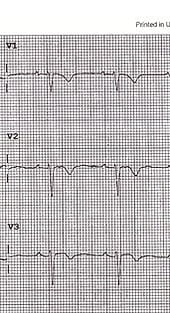

This ECG belongs to a 19-year-old male who presented to the Emergency Department (ED) with recurrent episodes of palpitations. Notably, he reported no chest pain or breathlessness at any time during the episodes, and there were no previous ECGs available for comparison. The patient was completely asymptomatic in between the episodes, and this ECG was taken while he was asymptomatic.

During his visit, the patient suddenly developed another episode of palpitations, prompting the need for a repeat ECG. Here's what was found:

ECG of the patient during the episode

(Courtesy of Dr. Chris Beng, Emergency Medicine Consultant, UK)

ECG Analysis

Upon closer examination, the following ECG abnormalities were observed:

2. Epsilon wave in V2 (a distinctive wave at the end of the complex and beginning of the ST segment)

3.L BBB Morphologyin VT ECG (Left Bundle Branch Block)